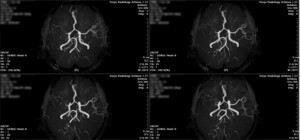

2018년 여주영상의학과 의원에서 종합검진을 받은 위의 사진을 블로그에 올렸다. 한국에서는 가장 큰 병원에 다니는 옛 회사동료에게 전화가 왔다. 뇌 전문의에게 이 사진을 보여주었더니, 대형 종합병원에 가서 꼭 진단을 받아야 한다는 말을 전하기 위해서 였다. 이 전화를 받고 20여년전의 일들부터 차근 차근 설명해 주었다. 나는 내가 고혈압이 있다는 사실을 몰랐다. 선교지로 나가기 얼마 전인 2002년에야 나는 고혈압이라는 사실을 알았다. 하나님이 나에게 선물과 같은 사건을 통해서 알려주신 것이다. 그해 겨울, 선교회에서 진행하는 훈련